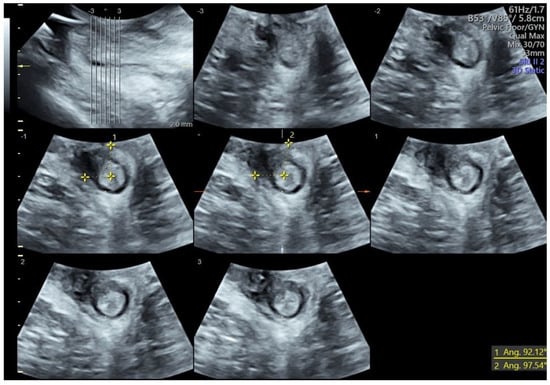

- Stickelmann, A.-L.; Kennes, L.N.; Hölscher, M.; Graef, C.; Kupec, T.; Wittenborn, J.; Stickeler, E.; Najjari, L. Obstetric Anal Sphincter Injuries (OASIS): Using Transperineal Ultrasound (TPUS) for Detecting, Visualizing and Monitoring the Healing Process. BMC Women’s Health 2022, 22, 339. [Google Scholar] [CrossRef] [PubMed]

- Ros, C.; Martínez-Franco, E.; Wozniak, M.M.; Cassado, J.; Santoro, G.A.; Elías, N.; López, M.; Palacio, M.; Wieczorek, A.P.; Espuña-Pons, M. Postpartum Two- and Three-Dimensional Ultrasound Evaluation of Anal Sphincter Complex in Women with Obstetric Anal Sphincter Injury. Ultrasound Obs. Gynecol. 2017, 49, 508–514. [Google Scholar] [CrossRef]

- Hakim, S.; Santoso, B.I.; Djusad, S.; Moegni, F.; Surya, R.; Kurniawan, A.P. Diagnostic Capabilities of Transperineal Ultrasound (TPUS) to Evaluate Anal Sphincter Defect Post Obstetric Anal Sphincter Injury (OASIS)? A Systematic Review. J. Ultrasound 2023, 26, 393–399. [Google Scholar] [CrossRef]

- Volløyhaug, I.; Taithongchai, A.; Arendsen, L.; Van Gruting, I.; Sultan, A.H.; Thakar, R. Is Endoanal, Introital or Transperineal Ultrasound Diagnosis of Sphincter Defects More Strongly Associated with Anal Incontinence? Int. Urogynecol. J. 2020, 31, 1471–1478. [Google Scholar] [CrossRef]

- Abdool, Z.; Sultan, A.H.; Thakar, R. Ultrasound Imaging of the Anal Sphincter Complex: A Review. BJR 2012, 85, 865–875. [Google Scholar] [CrossRef]

- García-Mejido, J.A.; Gutiérrez Palomino, L.; Fernández Palacín, A.; Sainz-Bueno, J.A. Aplicabilidad de la ecografía transperineal en 3/4D para el diagnóstico de lesiones del esfínter anal durante el posparto inmediato [Applicability of 3/4D transperineal ultrasound for the diagnosis of anal sphincter injury during the immediate pospartum]. Cir. Cir. 2017, 85, 80–86. [Google Scholar] [CrossRef]